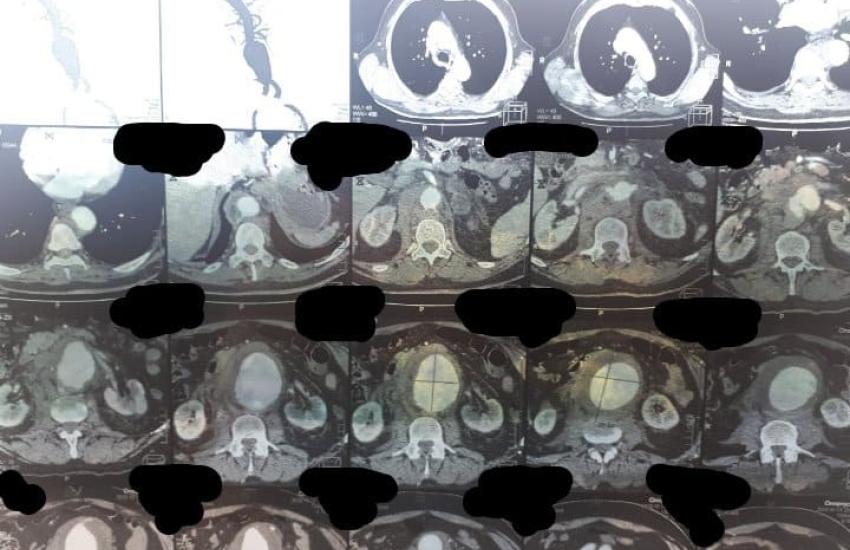

По приїзду в обласну лікарню хворому одразу зробили КТ, зібрали консиліум лікарів. Встановлений діагноз: атеросклеротична аневризма черевного відділу аорти з розривом. Прийняте рішення про оперативне втручання. Лікарям одразу стало зрозуміло, що операція буде дуже складною через те, що аневризма розпочиналася від рівня відходження ниркових артерій і закінчувалася біфуркацією аорти. Це потребувало високого перетискання аорти під час операції над рівнем ниркових артерій, виключення нирки із загального кровотоку. Черкаські хірурги звернулися за допомогою до своїх колег Олександра Ліксунова та Андрія Ратушнюка з Національного інституту хірургії та трансплантології ім. О.О. Шалімова. Незважаючи на те, що київські колеги щойно повернулися в Київ з Миколаєва, вони вже на ранок вирушили до Черкас, адже, рятувати чоловіка потрібно було в найкоротший термін.

14 жовтня 2020 пацієнту було проведене оперативне втручання – видалення аневризми з заміщенням її судинним протезом. Операція потребувала відключення кровотоку в нирках на 25 хв, була складною та тривала 2 години. Вона пройшла успішно та без ускладнень.